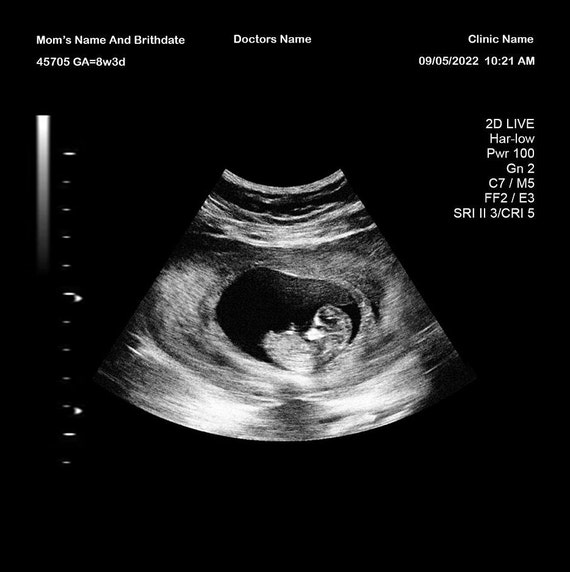

Due to the prank trend on social media fake ultrasounds have become quite common.

From 4 weeks to 24 weeks and everything in between Baby. How To Tell A Fake Ultrasound. The fake twin ultrasound is an image that can be used as a prank and looks like a real ultrasound with twins.

How To Spot A Fake Ultrasound. Ultrasound exams that are done at a hospital will have the hospitals name the pts medical record number and other pertinent information. Greys Anatomy seems to think that when an ultrasound is being used every machine creates this noise.

Baby Maybe offers a completely free fake ultrasound maker - you can choose an image add your. You can easily tell if it is fake if the same image. You might have heard of fake ultrasounds.

Theyre there to get pranks going and you probably dont want to be a victim. A fake ultrasound can help couples who have suffered miscarriage or those who are TTC on Trying to Conceive. How can you tell a fake ultrasound.

How Does My Fake Ultrasound Differ From A Real Ultrasound Baby Maybe